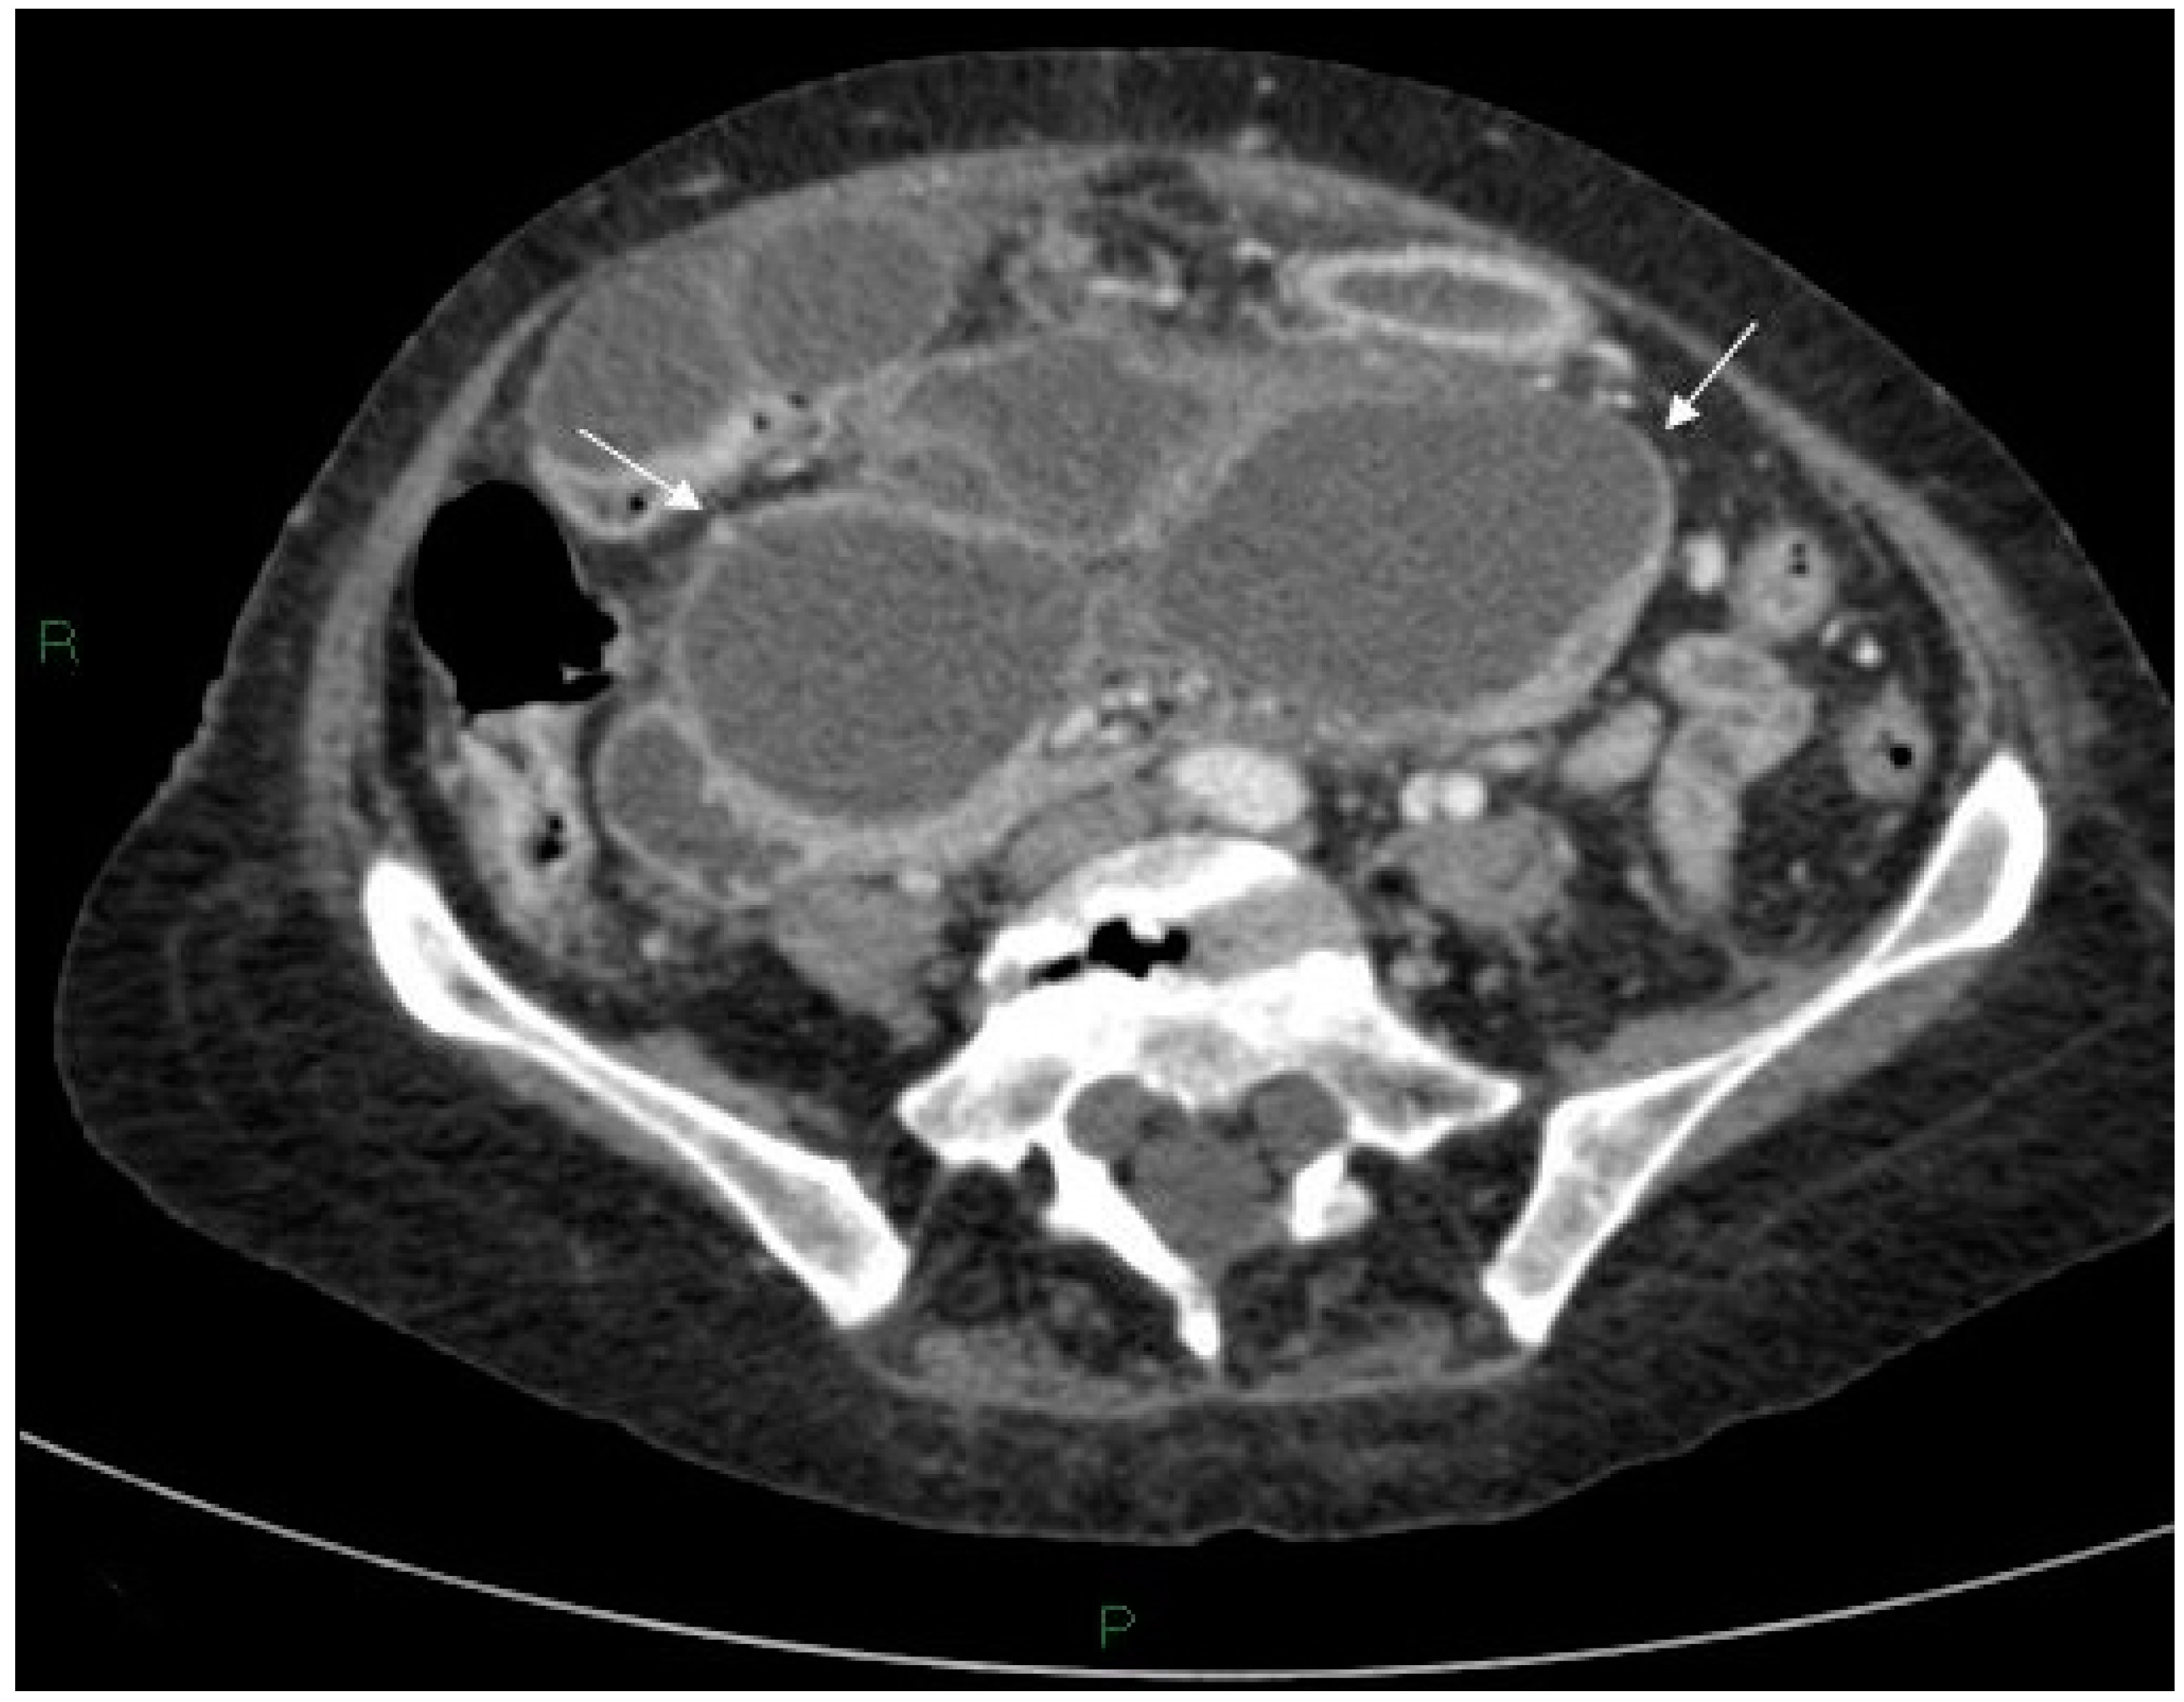

Figure 5.

Initially, Axial CT scan showing the stomach containing a nasogastric tube anterior to the cyst (large white arrow), free air (small white arrows) and inflammatory changes in the soft tissues between the stomach/duodenum and the cyst (black arrow).